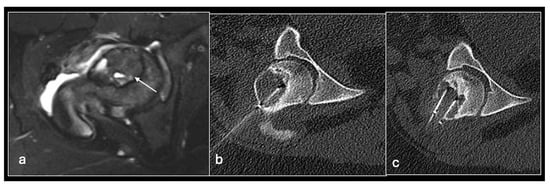

Figure 3. Sagittal T1 (a), T2 (b) and axial T2 (c) showing tumour (arrow) in the vertebral body and CT guided biopsy of the lesion (d).

Bone lesion biopsy is a similarly variable process. However, given that such lesions are almost invariably deep and typically have either a calcified component or lie behind a bony cortex, ultrasound is usually not a feasible option. Therefore, CT guidance is the workhorse of these procedures in our centre. As with soft tissue lesions, an initial planning scan is followed by local anaesthetic administration and then ‘CT fluoroscopy’ imaging as a percutaneous biopsy system is targeted to the lesion.

We use two main needle systems. Most bone lesions can be sampled with a T-Lok eight-gauge system with an inner diamond-tipped stylet and outer cannula. This is inserted through the cortex overlying a bone lesion. Once in the lesion, the stylet is removed and the cannula is advanced to the deep wall of the lesion aiming to trap the core against normal bone on either side. A tray is then inserted through the cannula to acquire the sample. Both tray and cannula are withdrawn together and the sample is then deposited into the relevant histopathology or microbiology pots (Figure 2 and Figure 3). Typically, only one sample is needed unlike in a soft tissue biopsy.